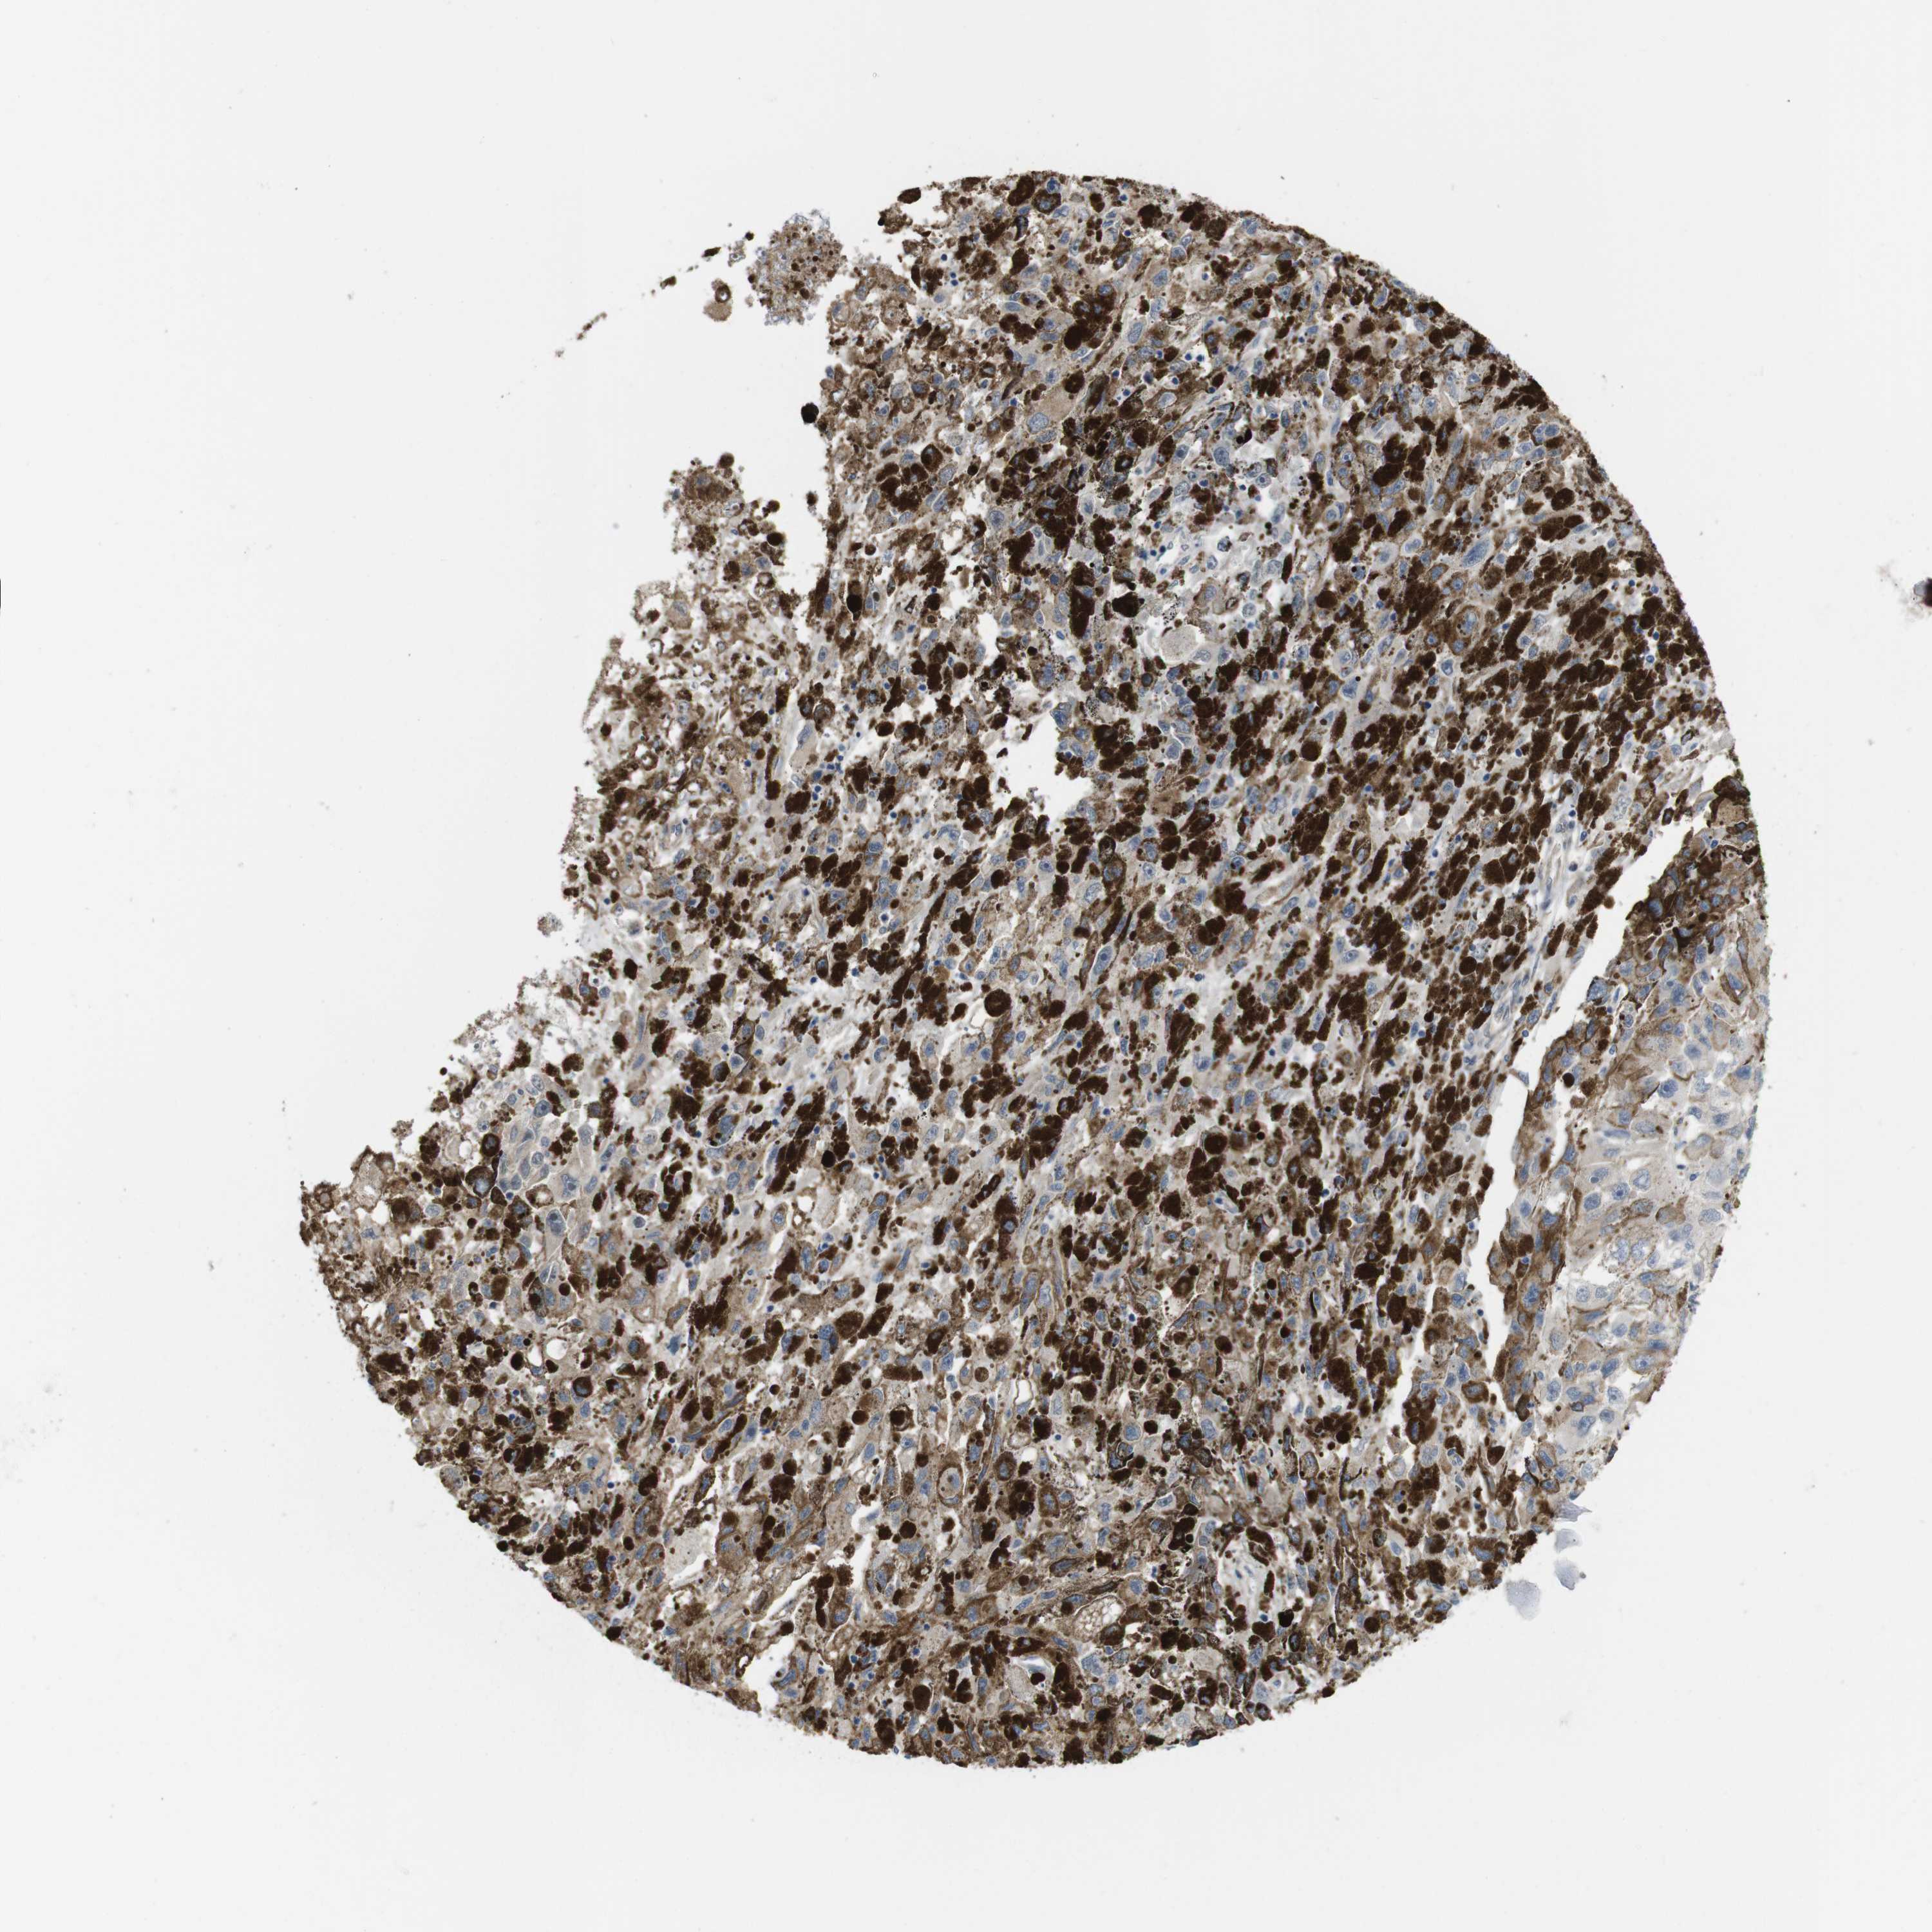

MELANOMA - Protein expressioni

A mouse-over function shows sample information and annotation data. Click on an image to view it in a full screen mode. Samples can be filtered based on level of antibody staining by selecting one or several of the following categories: high, medium, low and not detected. The assay and annotation is described here.

Note that samples used for immunohistochemistry by the Human Protein Atlas do not correspond to samples in the TCGA dataset.

Antibody stainingi

Antibody staining in the annotated cell types in the current human tissue is reported as not detected, low, medium, or high, based on conventional immunohistochemistry profiling in selected tissues. This score is based on the combination of the staining intensity and fraction of stained cells.

Each image is clickable and will lead to virtual microscopy that enables deeper exploration of all samples and also displays staining intensity scores, fraction scores and subcellular localization as well as patient and tissue information for each sample.

Antibody HPA014670

Staining

High

Medium

Low

Not detected

Intensity

Strong

Moderate

Weak

Negative

Quantity

>75%

75%-25%

<25%

None

Location

Nuclear

Cytoplasmic/membranous

Cytoplasmic/membranous,nuclear

Malignant melanoma, NOS

Malignant melanoma, Metastatic site